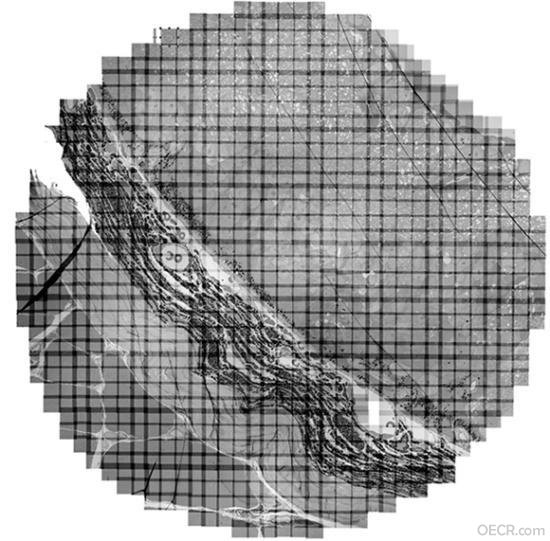

GMT+8, 2025-12-24 15:41